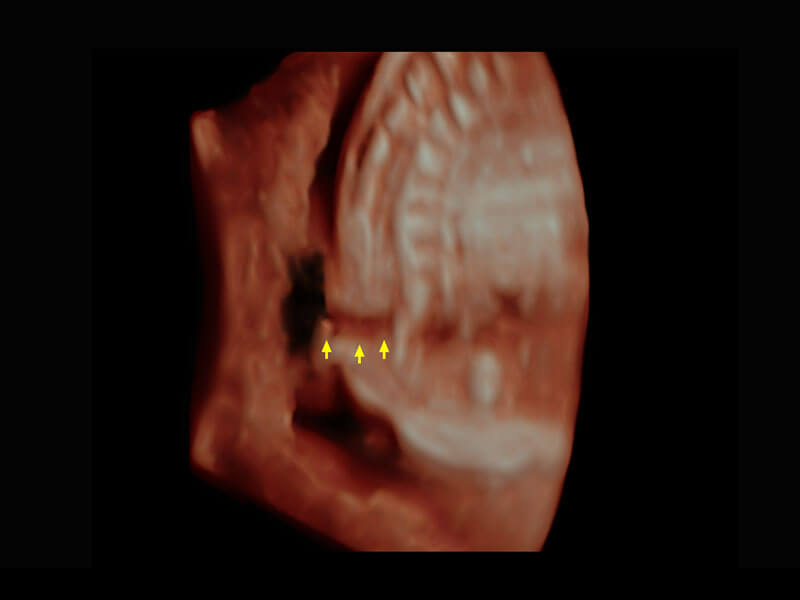

早孕-胎心